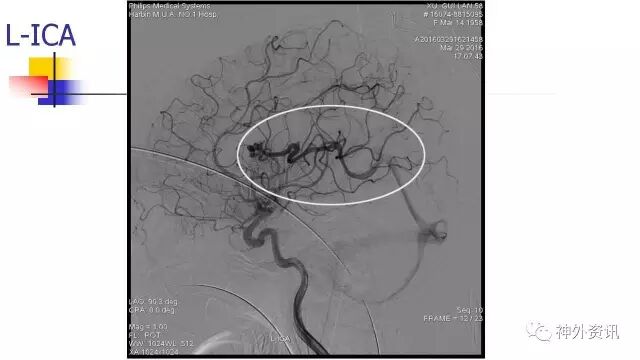

L-ICA动态

斜位动态